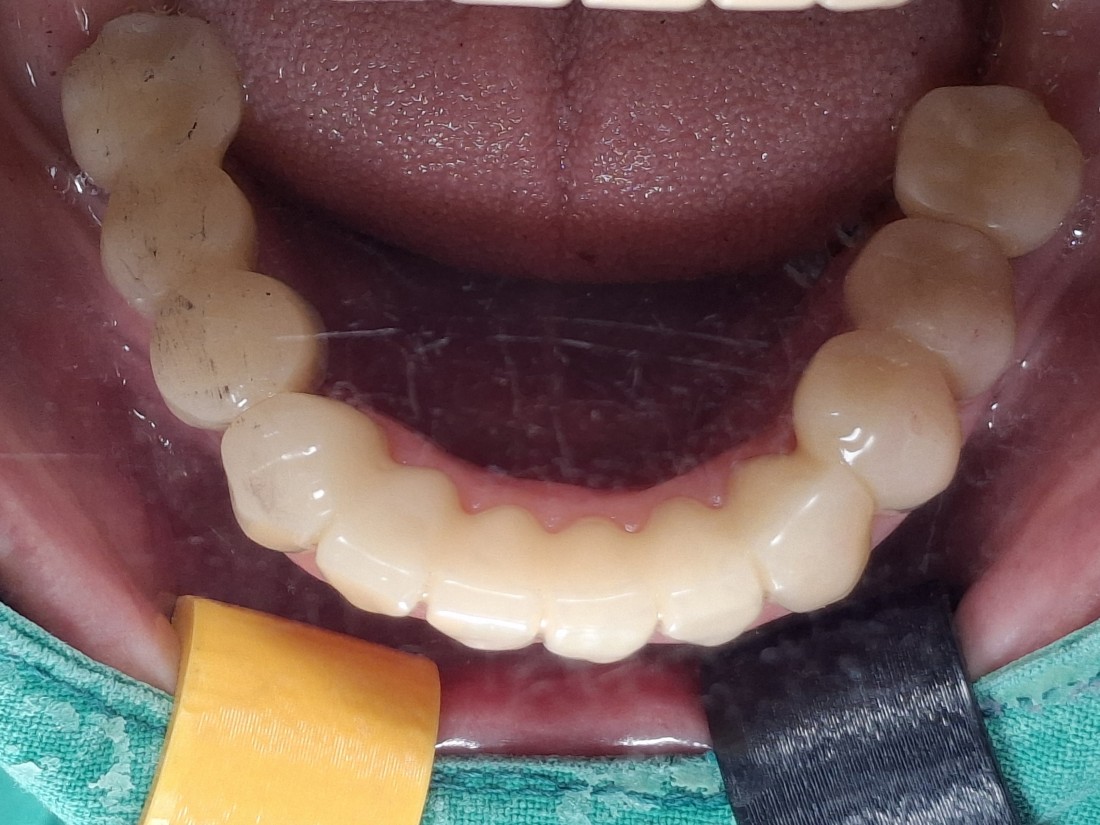

광주 상악임플란트 치과는

전체 임플란트 수술도

단 2번의 수술만으로

완성합니다.

광주 상악임플란트 치과에서는

위 / 아래 전체 임플란트를

붓기, 출혈, 통증을 최소화할 수 있는

디지털 가이드 임플란트 수술방법으로

단 2번의 수술만으로 완성하고 있습니다.